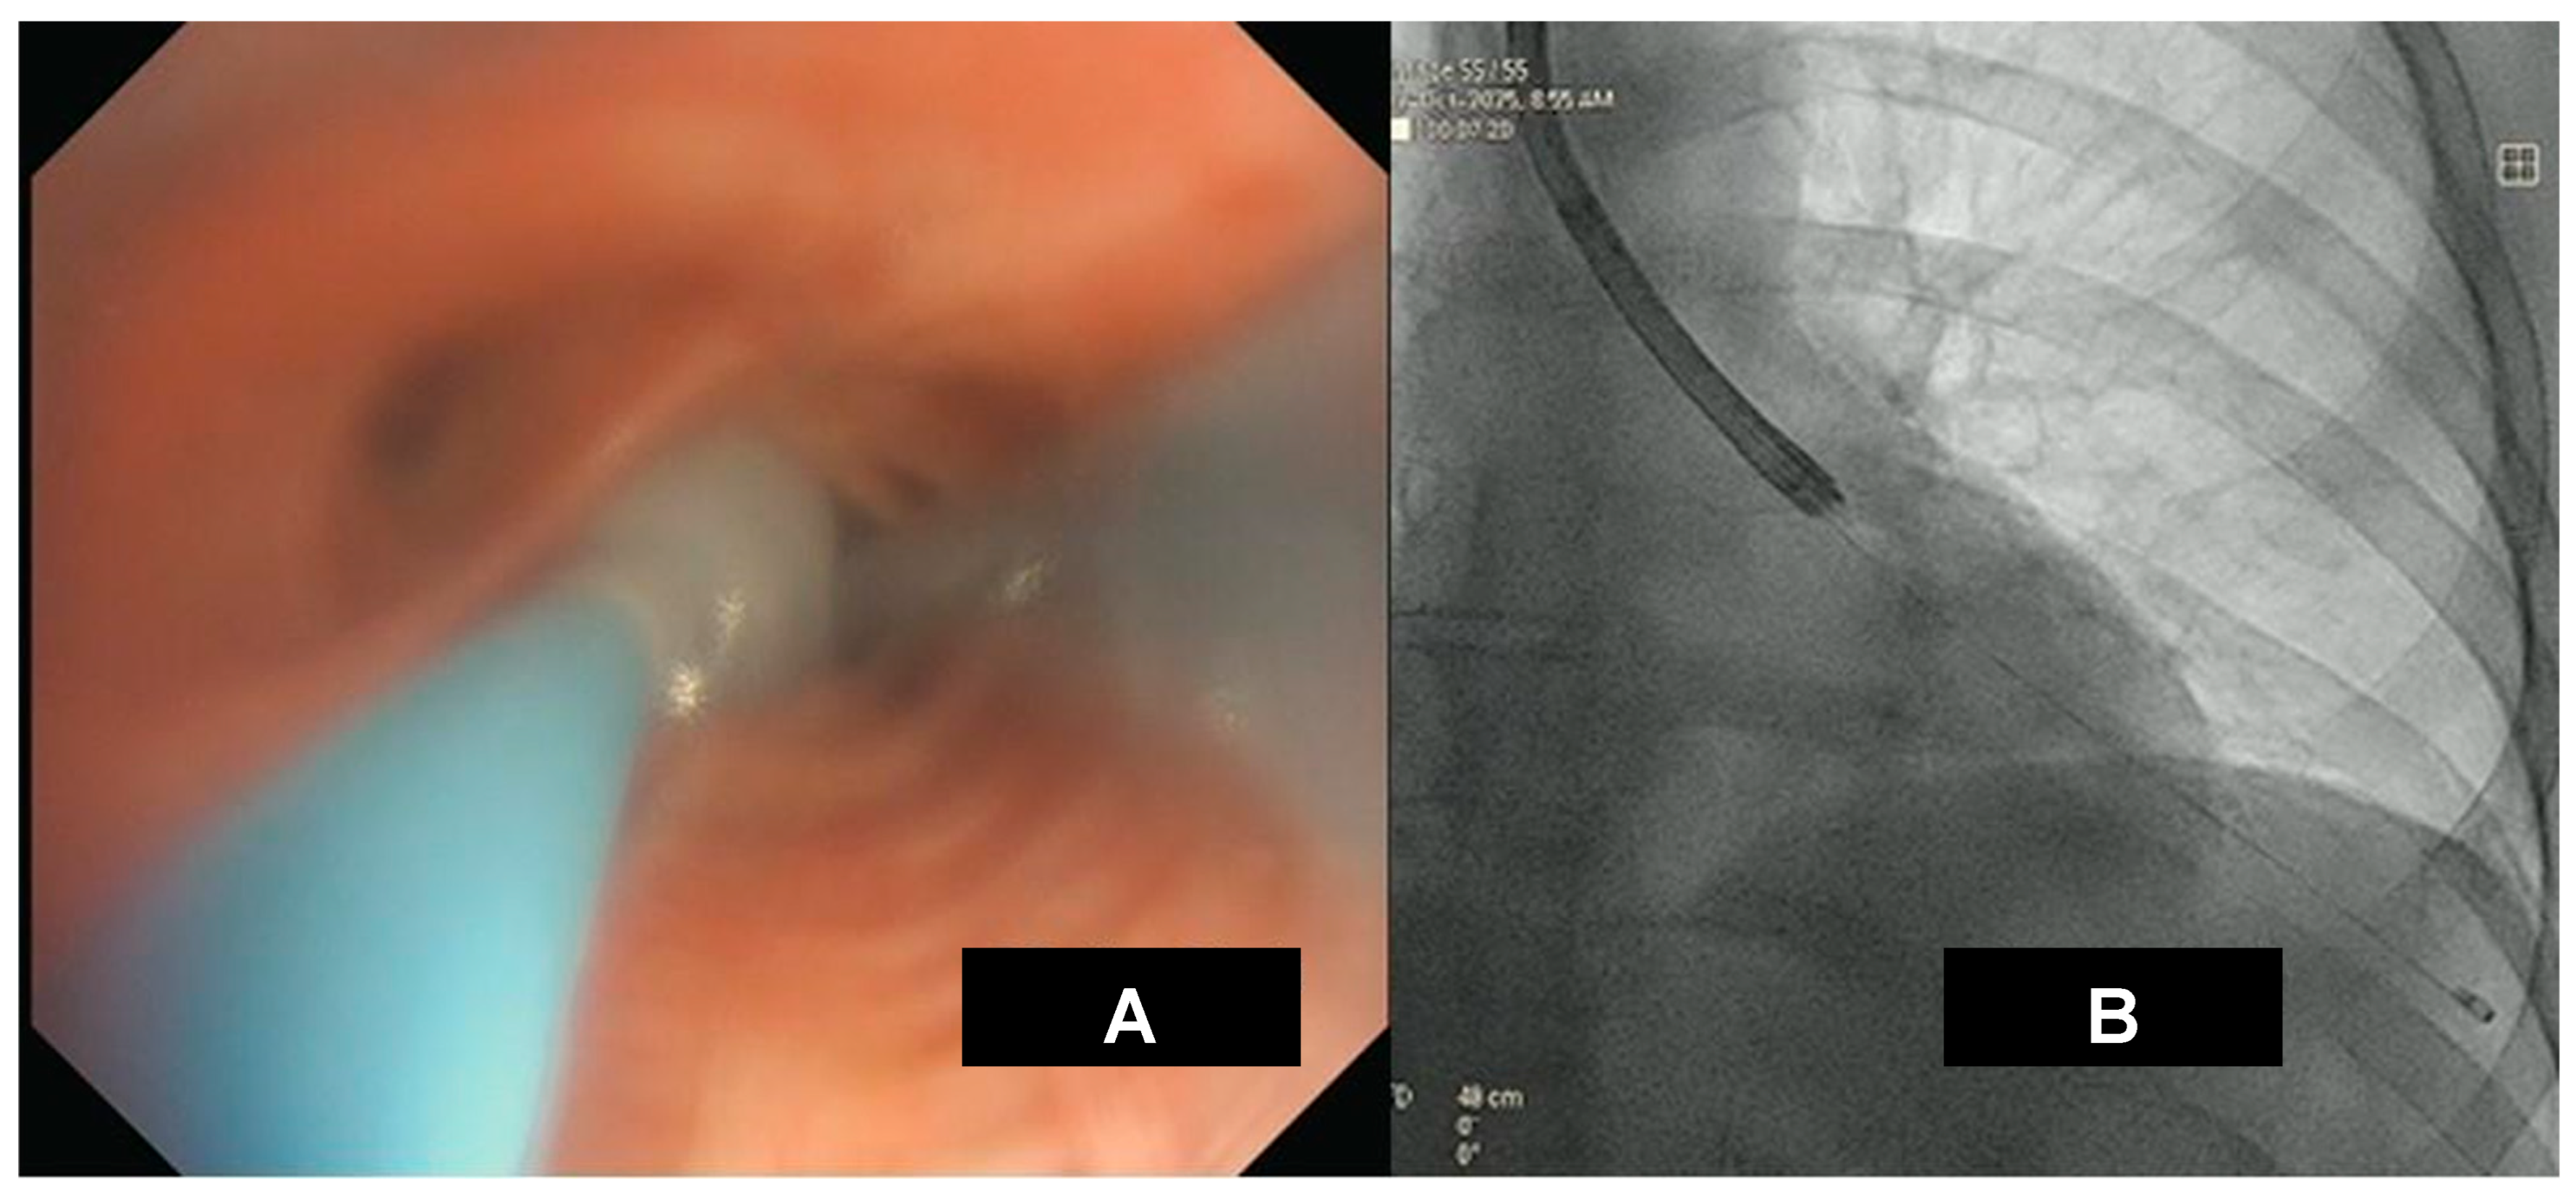

COVID-19 disease is an infection caused by the SARS-CoV-2 coronavirus that may develop subsequent complications involving different organ systems after recovery. These complications include myocarditis, myositis, and brain, kidney, and liver disorders. Pulmonary fibrosis is the major long-term complication of COVID-19 disease (Figure 1).

Figure 1. Picture depicting lung involvement in COVID-19 infection leading to interstitial lung disease.